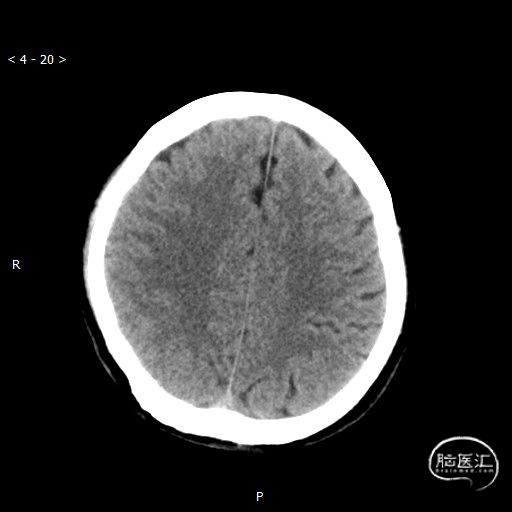

头颅CT(2020-05-12)出院:

右侧基底节区(尾状核头、右侧豆状核区)及右侧颞叶见斑片状低密度影,较2020-05-08片相比范围变化不大,边缘较前模糊不清,右侧豆状核区局部见小斑片状高密度影,较前密度减低,右侧脑室受压变窄,中线结构居中。

右侧基底节区及右侧颞叶脑梗死介入术后复查;右侧豆状核区小片高密度影,较前密度减低。